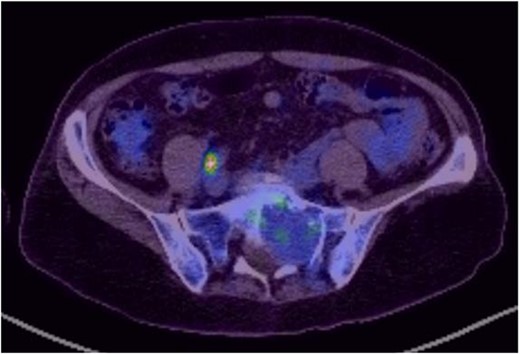

Reviews in July 2019 (with an MRI scan in December 2019) and December 2020 confirmed no neurological deterioration but some increased back and leg pain when standing for some time. A repeat MRI scan confirmed an increase in the size of the lesion (Figs 1 and 2). A biopsy was arranged with a plan for a follow-up surgery. Results of the CT-guided biopsy indicated a diagnosis of metastatic malignant melanoma. Discussions with the patient did not localise any skin lesion responsible for the metastatic deposit, an F18-fluorodeoxyglucose positron emission tomography (18F-FDG PET/CT) scan and a conventional computed axial tomography (CT) scan was organised (April 2021), which revealed sacral destruction and no other deposits in the chest, abdomen and pelvis (Figs 3 and 4). Our patient had a reported SUV of 3.6, indicating a malignant lesion that was then confirmed operatively.

MS comprises <1% of primary peripheral sheath tumours. The most common sites are cervical and upper thoracic spinal nerves with 30–40 years being the most common age group of occurrences [1, 3, 9]. The MRI characteristics of high signal on T1WI and low signal on T2WI with homogenous enhancement with contrast are well known. Our patient was in an older age group during presentation and had no skin deposits. Whereas a diagnosis was made on biopsy, it is also possible to use the FDG uptake on PET/CT imaging to determine the benign or malignant nature of the tumour [1]. The standardised uptake value (SUV) is a simple way of determining activity in PET imaging, most commonly in FDG imaging, and can predict the histologic response [10, 11]. It is used to measure response of cancers to treatment and considered a semi-quantitative value as it is vulnerable to other sources of variabilities [10, 11]. Hamada et al. set the cut-off point to 3.0 for distinguishing benign and malignant lesions [12]. Whereas there is an overlap in the SUV cut-off point amongst various authors, there is also a wide variation between them [13, 14]. Ahmed et al. reported 0.33–3.7, whereas Aoki et al. reported 1.75 ± 0.84 [14, 15]. However, Aoki et al., in another paper, reported a wider range of 0.7–2.84 [13]. Our patient had a reported SUV of 3.6, indicating a malignant lesion that was then confirmed operatively.